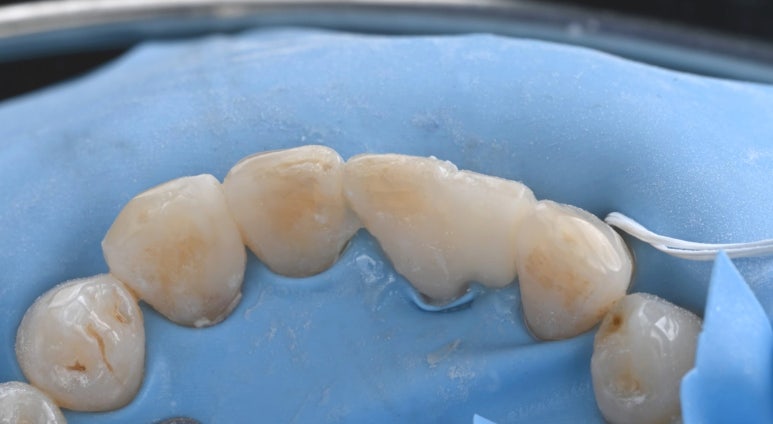

26.04.02 메릴랜드 브릿지 접착 후